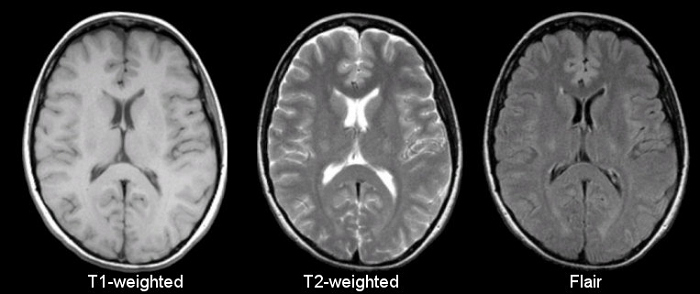

MRI图像的最优选择

在现实的临床中,CT、MRI、PET/SPECT各种影像都可以用来诊断老年痴呆症。通过比较,脑医生首先选择了MRI图像作为突破口。

王思伦表示:“MRI图像有很多优势:第一,在获取MRI图像时对人体没有放射性损伤。第二,MRI的结构性扫描在临床应用广泛,非常容易获得。第三获取成本低,时间短,通常情况下,患者拍MRI图像的成本在几百元左右,相比于PET\CT要便宜的多,另外拍摄时间短,不会对临床工作带来很多干扰。” 因此美国放射科学会也推荐结构MRI图像是诊断AD(阿尔兹海默症)的最佳影像学方式